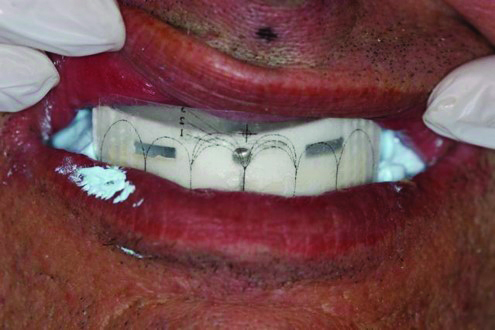

Fig 7. AvaDent’s proprietary impression system allows the dentist and patient to visualize tooth position, establish vertical, and the midline.

Figure 7

Fig 8. AvaDent’s impression system during the initial appointment.

Figure 8

All digital denture systems have a proprietary system for capturing all the key record information in one visit. Reverting back to the traditional record-taking denture protocol, the new digital workflow by the time of the denture set-up results in establishing: accurate models of the patient’s soft tissue, occlusal plane, vertical dimension and centric, midline and incisal tooth positions, proper lip support and choice of a mold and tooth shade. AvaDent and Pala each have their own methods for acquiring this data (Figure 7 through Figure 9).7,8 The key to a successful digital denture is accurately acquiring all the required records.